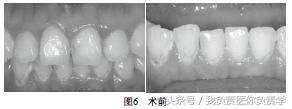

检查:11M,D,12M,D,13M,La,21M,D,22M,31M,D,La,32M,D,La,33M,41M,D,La,42M,D,La,43M,La均不同程度龋坏,质软,黄褐色。冷测正常,叩痛(-),不松动,牙龈无窦道。见图6。

口底唾液池浅,全口粘膜较干燥。口腔卫生一般,菌斑(+)。前牙区牙龈缘红肿,BI:2,全口PD:2~3mm。